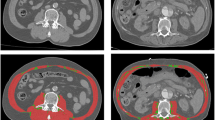

CT scans were imported from the local radiology system and assessed for quality. First, the third lumbar vertebra (L3) was identified on abdomen CT scans. This landmark was chosen because of its established correlation with whole-body muscle mass [17–19]. The L3 slice provides information on a number of muscles: the erector spinae-, quadratus lumborum-, psoas-, transversus abdominis-, interior- and exterior oblique-, and rectus abdominis muscles. The L3 slice was isolated and stored for later analysis.

CT scan analysis was performed by using Slice-O-matic version 4.3 and 5.0 (TomoVision, Montreal, QC, Canada) by trained personnel. Muscle tissue was identified by using boundaries in Hounsfield Units set to -29 to +150 [18]. The software computed a muscle surface area in cm2 by multiplying the pixel area by the amount of pixels identified as muscle.